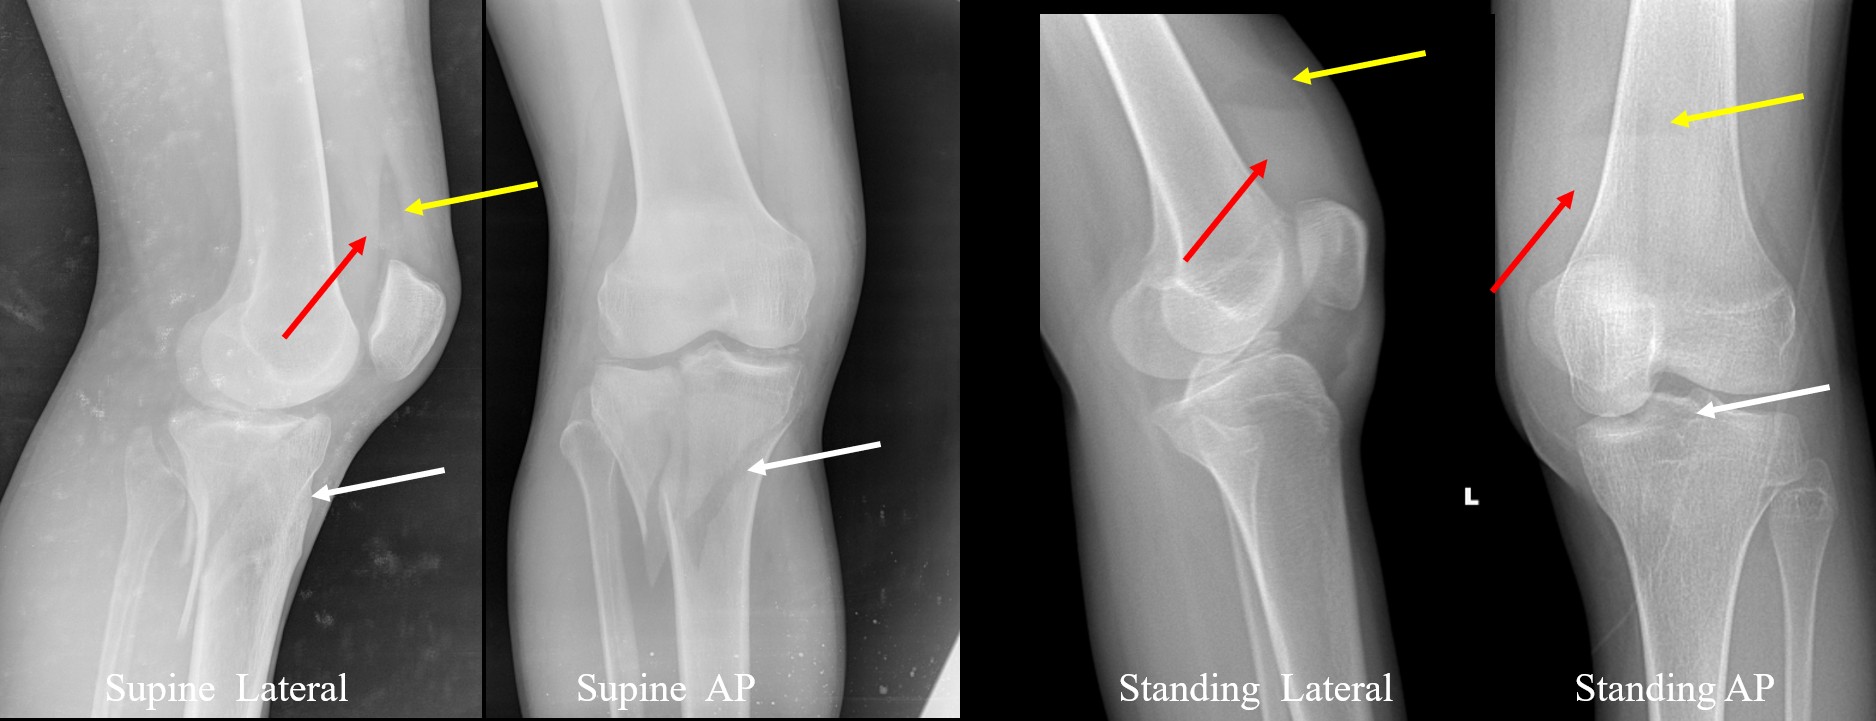

Definition Lipohemarthrosis refers to the presence of fat and blood within the joint space, resulting in a fat–fluid level due to density dif ...

Meniscal tears are among the most common knee pathologies encountered in musculoskeletal radiology, arising from trauma, sports injuries, degenerative ...